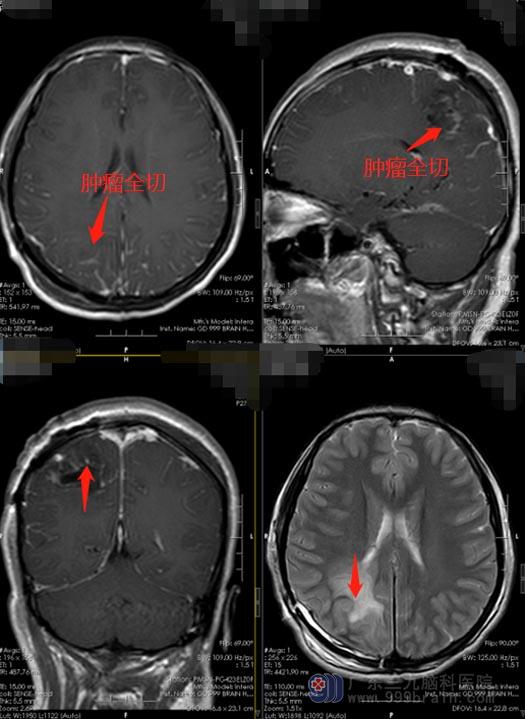

枕叶为视觉皮质中枢,枕叶病损时不仅发生视觉障碍,而且还会出现记忆缺陷和运动知觉障碍等症状。虽然小玲的视力还没有受到影响,但是应尽快地进行手术治疗,征得小玲及父亲母亲的同意, 2020月11月18日,鲁明主任主刀为小玲行“右侧枕叶占位病变切除术”,术后小玲恢复良好,四肢活动自如,病理报告提示:节细胞胶质瘤,WHOⅠ级。

节细胞胶质瘤是神经细胞和胶质细胞的混合性肿瘤,可发生于脑的任何部位,生长缓慢,常为小结节,边界清楚但无包膜,质较硬,常有囊变和钙化,大多数为良性肿瘤;多见于儿童及青少年,绝大多数发生于30岁前,主要临床症状是癫痫。

手术后的小玲没有再出现癫痫症状。他们长长地舒了一口气,压在心头的一块重重的石头终于卸了下来。